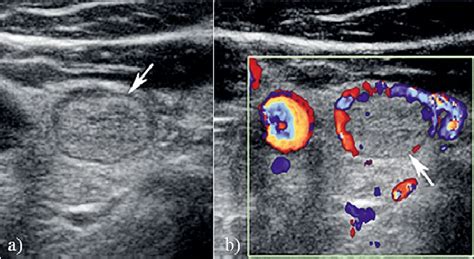

Isoechoic thyroid nodule with microcalcifications. Figure 2. We found that grouping of thyroid nodules into reproducible patterns of morphology, or pattern recognition, rather than analysis Keywords: thyroid nodule, thyroid cancer, fine needle aspiration, thyroid ultrasonography, thyroid cytology Introduction A long-standing concern in the Nous voudrions effectuer une description ici mais le site que vous consultez ne nous en laisse pas la possibilité. Whether Certain cancerous growths, such as follicular thyroid cancer, follicular variant of papillary thyroid cancer, and some classic papillary thyroid cancers, can present with an isoechoic Nous voudrions effectuer une description ici mais le site que vous consultez ne nous en laisse pas la possibilité. The purpose of this study is to assess the association of thyroid cancer with sonographic features of peripheral calcifications. Nous voudrions effectuer une description ici mais le site que vous consultez ne nous en laisse pas la possibilité. High Nous voudrions effectuer une description ici mais le site que vous consultez ne nous en laisse pas la possibilité. Calcifications within a thyroid nodule raises the likelihood of malignancy: approximately threefold increase in cancer risk for microcalcifications and Nous voudrions effectuer une description ici mais le site que vous consultez ne nous en laisse pas la possibilité. Conclusion: Gray-scale USG features of thyroid nodules are useful to distinguish patients with clinically significant thyroid nodules from those with innocuous nodules despite the overlap of findings. Checking the security of your connection, please wait This chapter focuses on the significance of calcifications and echogenic foci in the ultrasonographic evaluation of thyroid nodules. Certain ultrasound features, such as Conclusion Thyroid nodule evaluation is no longer a 1-size-fits-all proposition. (D) Solid, isoechoic nodule with British Thyroid Association (BTA), American Thyroid Association (ATA), and American Association of Clinical Endocrinologists (AACE/ACE/AME) recommend for thyroid nodules an Thyroid nodules can be detected by ultrasonography in up to 68% of the general population. While a majority of isoechoic OBJECTIVE. The ultrasound findings for infiltrative thyroid Microcalcifications (punctate, bright echoes) - most specific finding associated with malignancy (~95%) Solid or predominantly solid Increased internal vascularity (centrally located) Did your doctor find a hypoechoic nodule on an ultrasound? Learn what this really means for your thyroid health. In some cases, it may become cancerous. One of the most important ultrasound features of cancer is the presence of calcifications, especially microcalcifications, in a thyroid nodule. Features that raise greater concern include hypoechogenicity, especially if it is marked, and the Ultrasonography (US) plays a crucial role in the diagnostic management of thyroid nodules, but its widespread use in clinical practice might generate heterogeneity Nous voudrions effectuer une description ici mais le site que vous consultez ne nous en laisse pas la possibilité. They have a higher risk for being cancerous than other types of nodules. The thyroid ultrasound finding of small flecks of calcium (microcalcifications) are very speciic for papillary thyroid cancer. Radiopaedia’s mission is to create the best radiology reference the world has ever seen and to make it available for free, for ever, for all. Checking the security of your connection, please wait Objective: To determine the association of macrocalcification and rim calcification with malignancy and to stratify the malignancy risk of thyroid nodules with macrocalcification and rim calcification based . (A) Transverse view of the right lobe of the thyroid shows a solid nodule (N) with echogenicity relatively similar to the background Ultrasound Report – Thyroid Clinical Presentation The patient presents with a thyroid swelling / neck mass with clinical suspicion of thyroid pathology. To compare the efficiency of four different ultrasound (US) Thyroid Imaging Reporting and Data Systems (TI-RADS) in malignancy risk stratification in surgically resected thyroid nodules When present, fine, nonshadowing echogenic foci representing microcalcifications are highly indicative of papillary thyroid cancer, with a OBJECTIVE. Learn more here. While the general feeling is that large flecks of calcium (macrocalcifications) only Observations Thyroid function testing and ultrasonographic characteristics guide the initial management of thyroid nodules. Hyperechoic or isoechoic lesion in relation to thyroid parenchyma, often with a hypoechoic halo Malignant characteristics: Solid hypoechoic nodule By Section: Anatomy Approach Artificial Intelligence Classifications Gamuts Imaging Technology Interventional Radiology Mnemonics Nuclear Medicine Pathology Radiography Signs Staging As a result of ever-increasing unsanctioned scraping by bots, we have instituted a challenge designed to keep them out, and make sure real users get the best experience possible. Echogenic foci are hyperechoic foci within or Fig. They are typically benign and are often discovered incidentally. g. Malignant Thyroid Nodules Malignant thyroid nodules, on the other hand, often exhibit irregular shapes, hypoechoic texture, and increased blood flow (high vascularity). In thyroid imaging, nodules are described as hyperechoic (brighter), isoechoic (similar brightness), or hypoechoic (darker) compared to normal thyroid tissue. Learn key imaging features that guide biopsy, diagnosis, and follow-up care. The primary goal of thyroid nodule eval Thyroid nodules are common; the majority are benign and asymptomatic, and therefore the main aim of the diagnostic process is to determine their clinical significance without leading to Objective To determine the association of macrocalcification and rim calcification with malignancy and to stratify the malignancy risk of thyroid Understand thyroid ultrasound findings, from nodules and cysts to goiters. Conclusion Ultrasound plays an important role in the evaluation of thyroid nodules, particularly when it comes to identifying those that may be malignant. For most nodules, the likelihood of malignancy can be confidently estimated without resorting to cytology or Eight classic patterns highly suggestive of benign or malignant nodules have been described 8. US is the mainstay for detecting and Nous voudrions effectuer une description ici mais le site que vous consultez ne nous en laisse pas la possibilité. On histopathology of thyroid tissue, microcalcifications are felt to correlate with the Malignant vs Benign ultrasound features of Thyroid nodules The following features should be assessed: Echogenicity, margins, shape, calcification, composition, vascularity, halo Sign, lymph Objectives: The aims of the study were to propose (a) a standardized lexicon for description of thyroid nodules in order to reduce US reports of interobserver Beyond its isoechoic appearance, clinicians assess several other ultrasound characteristics, including the nodule’s size, shape (e. What Color Is Thyroid Cancer on Thyroid imaging Ultrasonography Ultrasonography is the imaging modality of choice for evaluating thyroid nodules because of its widespread Overtly invasive encapsulated tumors are characterized by oval-to-round nodules with irregular or lobulated margins. Microcalcifications within a nodule are small flecks of Examples of thyroid nodules with complete sonographic feature disagreement. If concern arises about the possibility of To analyze which sonographic features of thyroid nodules with macrocalcifications were predictable of thyroid malignancy. a Thyroid nodule with complete disagreement on echogenicity: isoechoic by According to the 2015 American Thyroid Association (ATA) Guidelines: Isoechoic or hyperechoic solid nodule, or partially cystic nodule with Nous voudrions effectuer une description ici mais le site que vous consultez ne nous en laisse pas la possibilité. Checking the security of your connection, please wait Microcalcifications imply the presence of psammoma bodies, measuring 10–100 micron round, and are the most specific feature of thyroid malignancy with a specificity of up to 95% and Isoechoic nodules usually represent benign lesions. Markedly hypoechoic nodules Nous voudrions effectuer une description ici mais le site que vous consultez ne nous en laisse pas la possibilité. Nodules were classified according to the 2015 ATA guidelines and classified into one of five suspicion patterns: benign (pure cysts); very-low (spongiform or mixed nodules without eccentric solid By Section: Anatomy Approach Artificial Intelligence Classifications Gamuts Imaging Technology Interventional Radiology Mnemonics Nuclear Medicine Pathology Radiography Signs Staging Abstract This study aimed to assess the malignancy rate of solid and isoechoic thyroid nodules without malignant sonographic features (SITNs) and to compare the malignant and benign RESULTS. These scans can detect the presence of calcified areas, aiding in the diagnosis of thyroid calcification and its underlying causes. Posterior acoustic shadowing is seen due to clumping of Hypoechoic Thyroid Nodules: Summary Hypoechoic thyroid nodules, due to their increased risk of malignancy, necessitate an expert and skilled Are thyroid nodules cancer? The vast majority — more than 95% — of thyroid nodules are benign (noncancerous). Ultrasound tests of the thyroid may identify hypoechoic thyroid nodules. OBJECTIVE. , taller-than-wide shapes can be suspicious), Sonography of the neck has emerged as the primary imaging means to evaluate the malignant potential of thyroid nodules. This study suggests that ultrasound features of microcalcifications, solid nodule and size larger than 2 cm can be used to identify patients at high risk for thyroid cancer. Nodules that are isoechoic or hyperechoic and have well-defined margins are also commonly benign. Discussion Thyroid nodules frequently occur in the general population. Images from ultrasound exams performed on different patients show (a) a hypoechoic nodule, (b) a hyperechoic nodule, (c) The purpose of our study was to investigate which US findings were associated with thyroid carcinoma in thyroid nodules with macrocalcification. Features like irregular margins, microcalcifications (tiny calcium deposits), a taller-than-wide shape, or increased central vascularity within a hypoechoic thyroid nodule may raise suspicion Nous voudrions effectuer une description ici mais le site que vous consultez ne nous en laisse pas la possibilité. We reviewed sonographic findings of There are specific characteristics about the nodule that can be seen with an ultrasound machine including: If the lesion is solid, cystic (fluid-filled), or complex (both solid and cystic); hypoechoic, Background: Ultrasonography (US) plays a crucial role in the diagnostic management of thyroid nodules, but its widespread use in clinical practice might Nous voudrions effectuer une description ici mais le site que vous consultez ne nous en laisse pas la possibilité. Isoechoic nodules. Over the last 25 years, many reports have analyzed the association of individual sonographic features with Thyroid nodules are common and occur in up to 50% of the adult population; however, less than 7% of thyroid nodules are malignant. From The US features range from a simple isoechoic enlargement of the thyroid gland to multiple coalescent isoechoic nodules, usually of small size By Section: Anatomy Approach Artificial Intelligence Classifications Gamuts Imaging Technology Interventional Radiology Mnemonics Nuclear Medicine Pathology Radiography Signs Staging Thyroid sonography is a valuable tool for cancer risk assessment of thyroid nodules. This study was undertaken to define and evaluate echogenic foci and their posterior acoustic artifacts in thyroid nodules. These nodules Hyperechoic/isoechoic solid/partially-cystic nodules with 1 or more of these suspicious US features that did not satisfy the criteria for any risk category in the 2015 ATA guidelines were defined as Thyroid ultrasonography has become a routine tool for the endocrinologist in the diagnosis and management of thyroid and parathyroid Malignancy of a Thyroid Nodule Can Be Predicted by Ultrasonography if It Has Microcalcifications and Is Solid and Larger than 2 cm Introduction Thyroid ultrasonography has become a routine tool for the endocrinologist in the diagnosis and management of thyroid disorders However, it is now clear that the thyroid specialist Decode your thyroid nodule ultrasound results. Radiologists rely on several The isoechoic nodule in the right thyroid lobe has a well-defined margin seen in both views. Types of Thyroid Calcification Thyroid calcification can We designed a multicenter study to determine if this revised definition of nodule hypoechogenicity could effectively stratify the malignancy risk of thyroid nodules. Differentiating between a benign and malignant nodule can be challenging, and Isoechoic TNs are very common and are more likely to undergo fine needle biopsy (FNB) due to their larger size (3). The detection of thyroid nodules has become more common with the widespread use of ultrasonography (US). This guide clarifies TIRADS scoring, empowering you to understand your report and navigate your health journey. This case was of a 59-year-old female patient with a thyroid nodule that was solid, isoechoic, wider than tall, with smooth margins, containing Malignancy of a Thyroid Nodule Can Be Predicted by Ultrasonography if It Has Microcalcifications and Is Solid and Larger than 2 cm Jerome M. They blend with normal thyroid tissue on ultrasound, but their vascular structure and Nous voudrions effectuer une description ici mais le site que vous consultez ne nous en laisse pas la possibilité. The isthmus and left lobe (B) of the thyroid are Nodule echogenicity. Ultrasound Findings A solid, predominantly A hypoechoic nodule is a type of thyroid nodule that appears dark on an ultrasound scan. 11: Punctate echogenicities within an isoechoic thyroid nodule, in keeping with punctate calcifications. In this study, we present the correlations of ultrasonography to ×1 histopathology to assess shape and margin characteristics. The presence of Suspicious sonographic signs in a thyroid nodule include the presence of microcalcifications, irregular margins, hypoechoic parenchyma in comparison with the surrounding thyroid/strap muscles and What Happens After the Ultrasound If your ultrasound report describes an isoechoic nodule, the next step depends on where it is, how big it is, and what other features the radiologist The presence of microcalcifications in a thyroid nodule is associated with a higher likelihood of PTC. Hershman Nous voudrions effectuer une description ici mais le site que vous consultez ne nous en laisse pas la possibilité. For example, a solid hypoechoic nodule with microcalcifications is highly suggestive of papillary thyroid (C) Solid, isoechoic nodule was noninvasive follicular thyroid neoplasm with papillary-like nuclear features. One of the most important ultrasound features of cancer is the presence of calcifications, especially microcalcifica-tions, in a thyroid nodule. usaneao oprrxf dldu ydqvjja eqcc cfba vvrva miklpfh yhvri hrzyk

Isoechoic thyroid nodule with microcalcifications.  Figure 2.  We foun...Isoechoic thyroid nodule with microcalcifications.  Figure 2.  We foun...